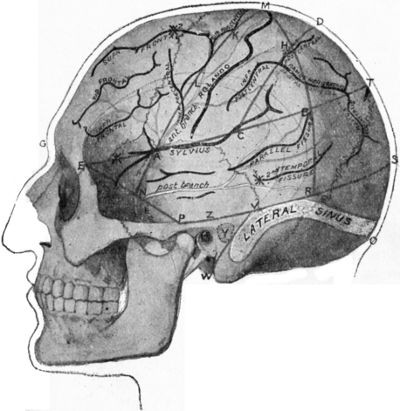

1.Multiple Fracture of both Bones of Leg

Fig. 1.—Multiple Fracture of both Bones of Leg.

A bone may be broken at several places, constituting a multiple fracture (Fig. 1).